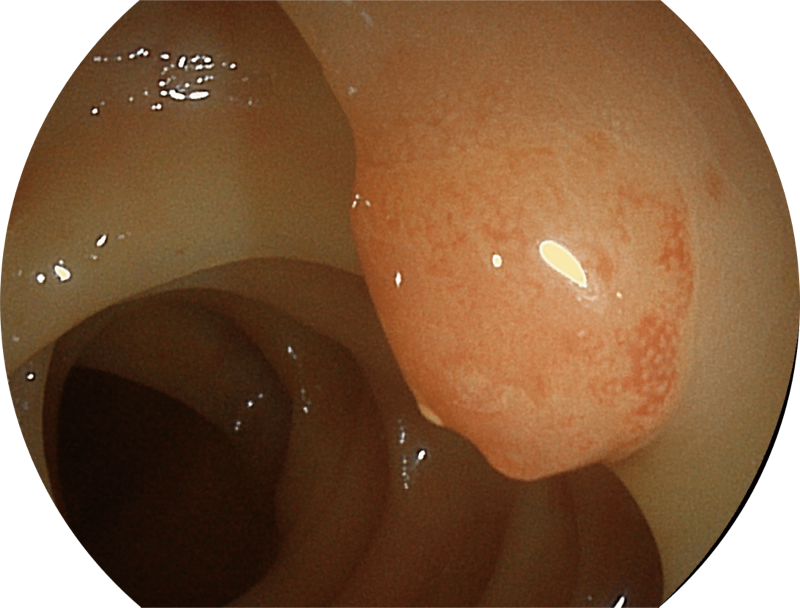

(Spectral Focused lmaging, SFI)

能够凸显黏膜浅层和中层血管轮廓,适用于中、远景观察下的病灶识别和早癌筛查。

白光图像

SFI图像